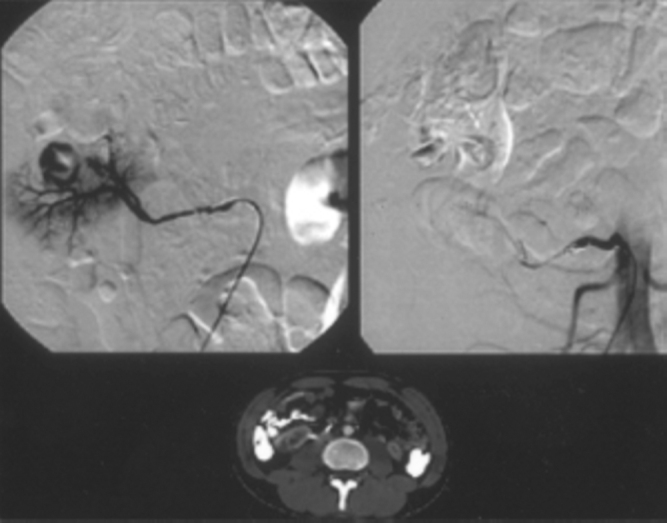

Endoluminal repair by stent graft is an emerging strategy in treatment of pseudoaneurysms. A stent graft is a metallic stent with a biologically compatible polymer cover usually made of polyester or polytetrafluoroethylene. The polymer cover limits myointimal ingrowth along the length of the treated segment, improving patency. In our series, Hemobahn/Viabhan endoprosthesis was used in five cases (Fig. 4A, Fig. 4B). The Hemobahn endoprosthesis is flexible, self-expanding, endoluminal prosthesis with an expanded polytetrafluoroethylene (ePTFE) tube inside a nitinol sinusoidally shaped helically wrapped stent [11].

Fig. 4A.

Doppler study of right popliteal region in a patient following fracture tibia, stabilized with screws shows popliteal artery pseudoaneurysm. Note the screw tip within the pseudoaneurysm. Axial CT shows extent and size of pseudoaneurysm. Sagittal MPR reveals the screw traversing the tibia with its tip within the pseudoaneurysm

Fig. 4B.

DSA image of right popliteal artery with arterial leak into pseudoaneurysm. DSA after stent graft shows complete isolation of pseudoaneurysms with patency of popliteal and tibial arteries. Plain film of right knee joint in flexion shows normal configuration of stent graft with no kinking.